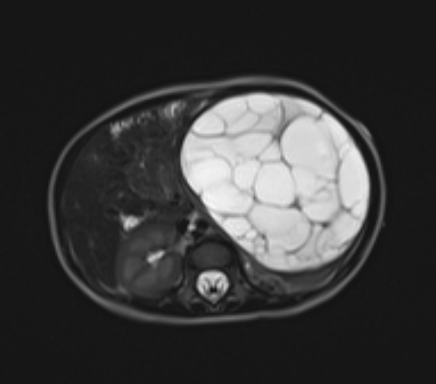

Multilocular Cystic Nephroma

• Michael Jackson disease

• Males 3 months - 5 years

• Middle aged women

• Multiloculated cystic mass

• Hemorrhage and necrosis uncommon

• DICER1 gene mutation

• 10% associated with pleuropulmonary blastoma

• Just looks like densely packed cysts together